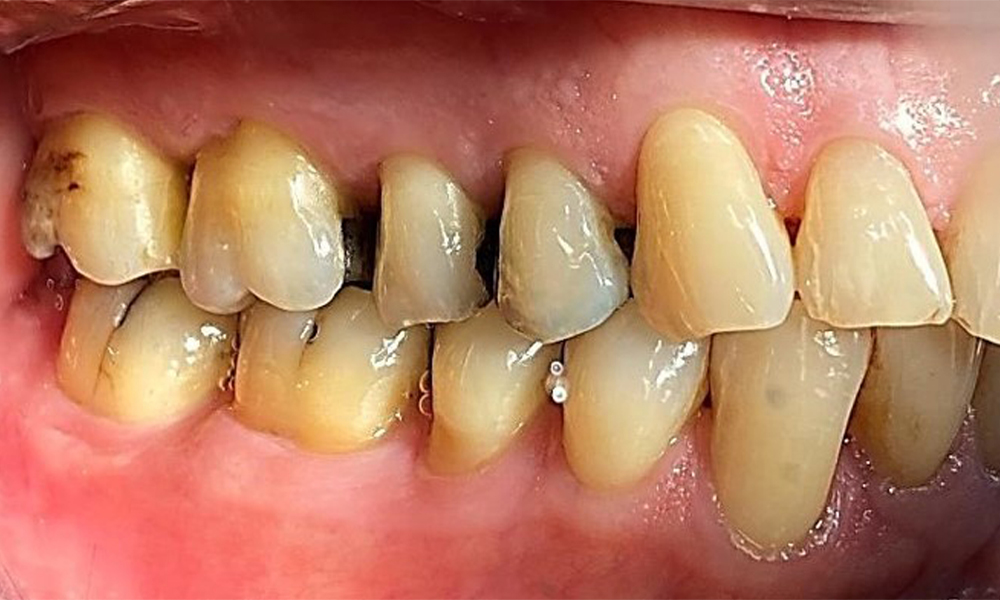

Lateralansicht rechts. Verlust der interdentalen Papillen. © Dr. R. Krapf

Abb. 3 Lateralansicht rechts. Verlust der interdentalen Papillen. © Dr. R. Krapf

Der Patient hat eine Parodontitis Stadium II, Grad B (5). Die klinischen Sondierungstiefen liegen mit 1-3mm im physiologischen Bereich. Lokalisierte Sondierungstiefen finden sich an 17 und 27 jeweils mesiopalatinal mit 5mm. Es liegen generalisierte Rezessionen von 1-3mm vor mit partiellem Verlust der Interdentalpapillen (Abb. 2, Abb. 3, Abb. 4)